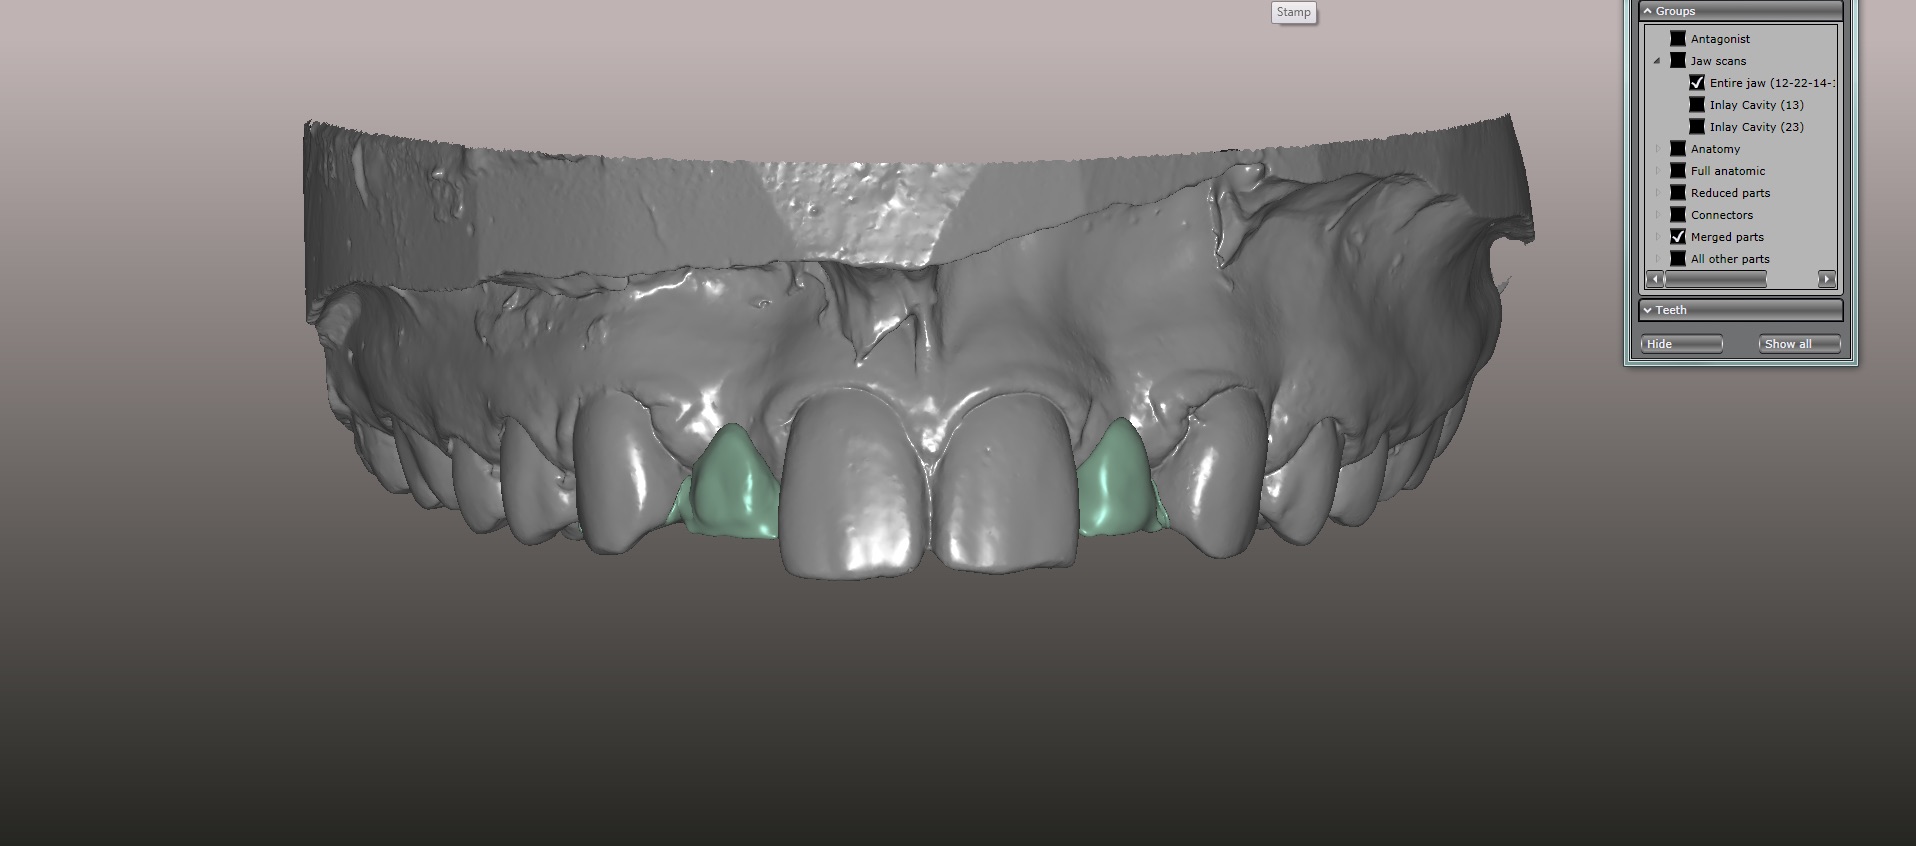

(15.) Models mounted in maximum intensity projection, allowing design of the retainer extensions on the lingual of the canines (in pink).

Figure 15

An approach utilizing CAD/CAM was employed to fabricate an accurate fitting, retentive, and esthetic ceramic single-wing resin-bonded bridge. Impressions were taken of the patient and scanned in the laboratory using maximum intensity projection. The scanned models were then used to design the final prosthetic frames utilizing EXOCAD software. The retainer positions and extensions were designed on the models based on the occlusal clearance (Figure 15). Next, the replacement tooth forms were chosen from a virtual library (Figure 16), and try-in PMMA bridge prototypes were milled in Primotec USA PMMA. This allowed for try-in of the design, adjustment of the contacts, and intraoral evaluation of the ridge contact (Figure 17). Once tried and idealized for both fit and occlusion, the design was sent back to the lab to rescan. Utilizing the software, a cut back was made on the lateral incisor (Figure 18), and a 0.3mm space was also virtually designed on the internal surface of the retainer wing to allow layering with feldspathic ceramic (Figure 19). The 0.2 mm internal edge of the wing was designed to be left intact to allow for precise seating and verification of fit on the model. After the frame was milled in zirconia (Zirconzahn, Prettau), it was verified on the model, and high fusing margin porcelain (Noritake CZR) was mixed with a clear utility wax and applied to the internal 0.3 mm depression. This was baked in the oven at a high temperature, allowing the wax to burn out and leaving the feldspathic ceramic fused to the internal surface of the retainer. Once cooled, this was checked for precise fitting on the model and adjustments were made to ensure full seating.